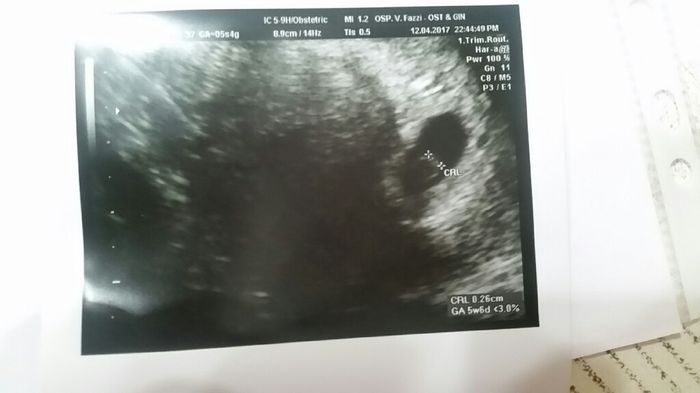

5 settimana ma la camera gestazionale dice che nn è completamente tonda. Mo ha dato 5 punture dj progesterone. Perderò il bambino? Non ci sto capendo niente

Ti. Capisco benissimo adesso ti.faccio.vedere anche la.mia era cosi....super piatta a qnd ho.fattp la.prjma.visita ero indietro di una settimana seconda.visita a 7+5 era cosi...a 13 settimane era cosi...adesso.sono a 16+4'..martedì prox.visita e non.bedo.l.ora.stao.solo.serena

Ieri ho fatto l'altra eco forse le punture fanno il loro effetto. Me ne ha aggiunte altre 2 ma dice che è cresciuto anche in 2 gg ...non mi ha fatto sentire il battito però ...

Tranquilla, anke la mia inizialmente non era completamente tonda. E poi con il progesterone (io mettevo gli ovuli d Progeffik, no le punture) è andata apposto. E ora paolino ha 5 mesi e dorme qua tranquillo nel divano Smiley winking stai serena, andrà tutto bene. Tu cmq cerca d stare a riposo e nn fare sforzi.

Io un consulto da un altro dottore lo farei subito per stare tranquilla..macché tonda, quasi tutte sono schiacciate, l'importante credo che siano le dimensioni, forse non é stato chiaro ..

Nooooo stai tranquilla anche a me aveva detto che era come.schiacciata fatto.cura di progesterone e ad oggi.sono a 16+2'.. vedrai stai serena

Anche io avevo camera gestazionale schiacciata. Anche a me diedero il progesterone per un po e riposo. Diciamo che non è uno degli inizi migliori.. Ma comunque il mio piccolo campione è qui con me e ha 14 mesi. Segui le indicazionibdel medico e riposati. In bocca al lupo.

Ciao Federica! Ma io non avevo la minima idra che la camera dovesse essere tonda... La mia non era per niente tonda alla prima visita di due settimane fa... Ti posto la foto, ma il gine non mi ha detto nulla a riguardo... C'è da dire che non ho mal di pancia, a te ha dato progesterone per dei dolori che hai?